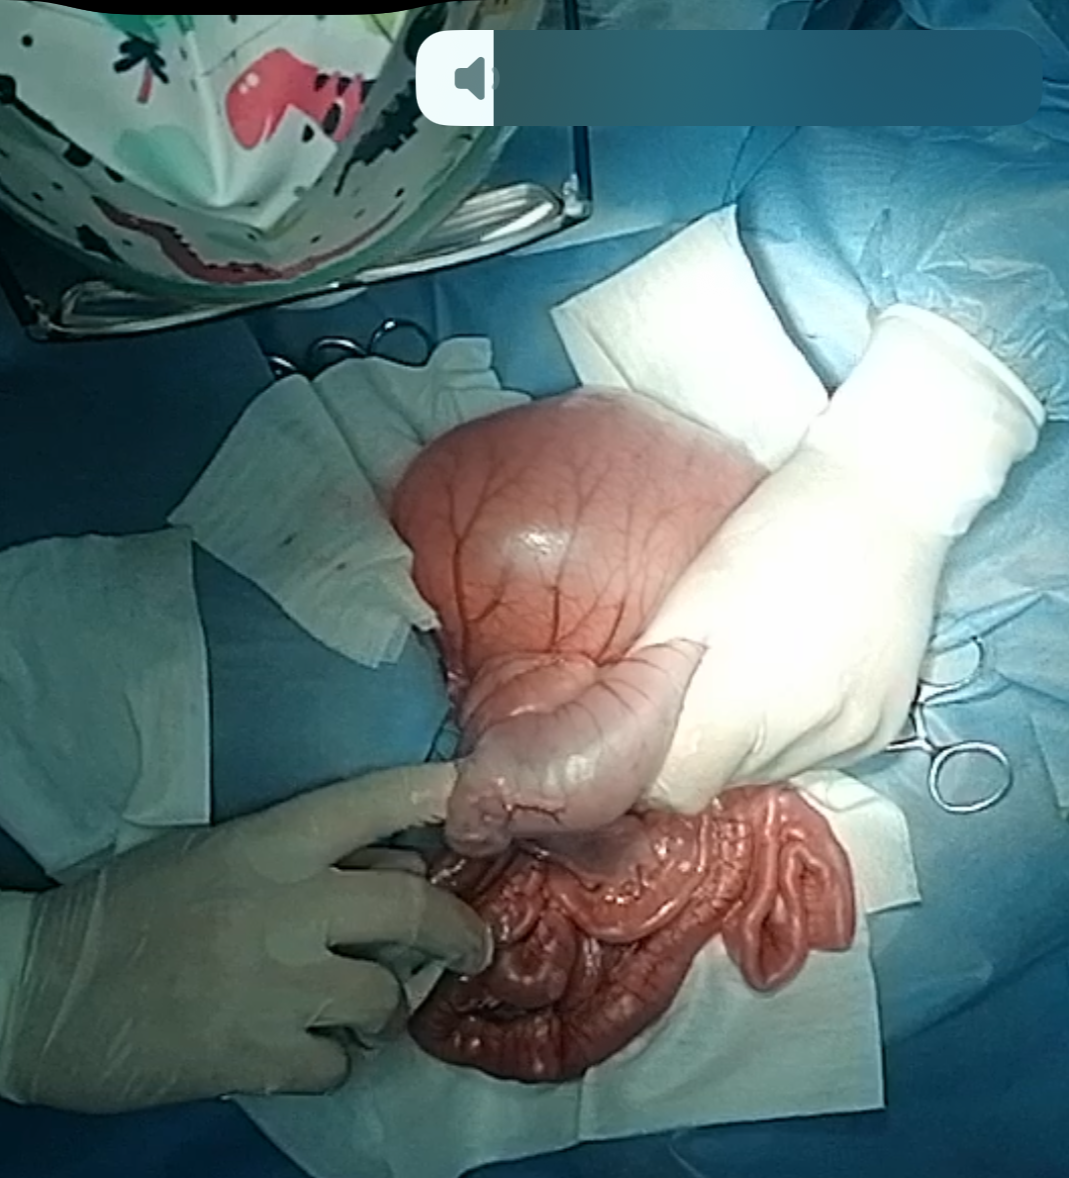

Emergency exploratory laparotomy was performed .

Two intussusceptions were identified — an ileo-cecal & ceco-colic intussusceptions The involved bowel was edematous and congested, but viable.

Gentle manual reductions was successfully achieved preserving the intestines and avoiding resection and anastomosis

1st segment of intussusception

1st segment of intussusception manually reduced

2nd segment of intussusception

2nd segment of intussusception various manipulations and attempts

2nd segment of intussusception manually reduced

the cecum is then reduced